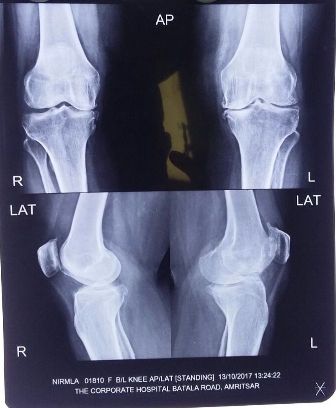

Patient : Mrs. Nirmala Devi

Age / Sex : 60 yrs Female

Procedure : Bilateral TKR Done

• Old age patient with Ligamentous Instability.

• Not able to bear weight from last 5 years.

• Walk with walker without weight bearing with flail knee.

• Total Knee Arthroplasty done with Tibial Stem.